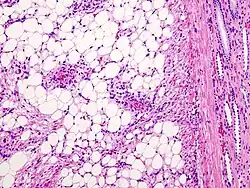

Angiomyolipom (HE-Färbung), links die Fettzellen, rechts die atypischen Blutgefäße

Mikroskopisch sind reife Fettzellen und glatte Muskelzellen nachweisbar. Die Muskelzellen können zahlreiche Mitosen aufweisen, daher kann der Tumor als Sarkom fehlgedeutet werden. Zusätzlich finden sich atypische Blutgefäße.